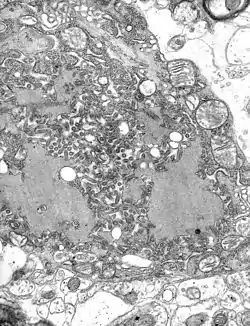

The rabies virus is the type species of the Lyssavirus genus, in the family Rhabdoviridae, order Mononegavirales. Lyssavirions have helical symmetry, with a length of about 180 nm and a cross-section of about 75 nm.[26] These virions are enveloped and have a single-stranded RNA genome with negative sense. The genetic information is packed as a ribonucleoprotein complex in which RNA is tightly bound by the viral nucleoprotein. The RNA genome of the virus encodes five genes whose order is highly conserved: nucleoprotein (N), phosphoprotein (P), matrix protein (M), glycoprotein (G), and the viral RNA polymerase (L).[27]

To enter cells, trimeric spikes on the exterior of the membrane of the virus interact with a specific cell receptor, the most likely one being the acetylcholine receptor. The cellular membrane pinches in a procession known as pinocytosis and allows entry of the virus into the cell by way of an endosome. The virus then uses the acidic environment, which is necessary, of that endosome and binds to its membrane simultaneously, releasing its five proteins and single-strand RNA into the cytoplasm.[28]

Once within a muscle or nerve cell, the virus undergoes replication. The L protein then transcribes five mRNA strands and a positive strand of RNA all from the original negative strand RNA using free nucleotides in the cytoplasm. These five mRNA strands are then translated into their corresponding proteins (P, L, N, G and M proteins) at free ribosomes in the cytoplasm. Some proteins require post-translative modifications. For example, the G protein travels through the rough endoplasmic reticulum, where it undergoes further folding, and is then transported to the Golgi apparatus, where a sugar group is added to it (glycosylation).[28]

When there are enough viral proteins, the viral polymerase will begin to synthesize new negative strands of RNA from the template of the positive-strand RNA. These negative strands will then form complexes with the N, P, L and M proteins and then travel to the inner membrane of the cell, where a G protein has embedded itself in the membrane. The G protein then coils around the N-P-L-M complex of proteins taking some of the host cell membrane with it, which will form the new outer envelope of the virus particle. The virus then buds from the cell.[28]